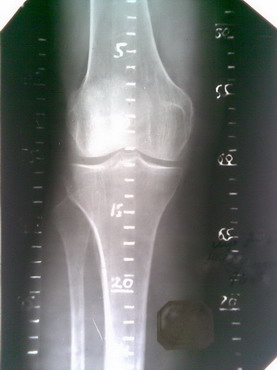

Рентгенограмма

Помог опыт юного радиолюбителя. Для изготовления необходимо приобрести текстолит (фольгированный односторонний) с нанесенным слоем меди с одной стороны (для т.н. печатных (монтажных) плат - продается в магазинах радиодеталей, да и все остальное купил там же, обошлось в сумму рублей 70). Выпиливается полоса по необходимой ширине и длине. В данном примере шириной 1,5 см, длина 25 см (длиннее заготовки не нашлось, 3 шт). Затем цапон-лаком по меди (предварительно пройтись шкуркой, а то краска потом может отвалиться) наноситься гусиным пером (иглой или другим подручным средством) необходимый рисунок (метки, цифры - аккуратнее всего получилось бы у художника). Иногда лак растекается, страшного ничего нет, когда высохнет - можно поправить (счистить), например скальпелем. Говорят, что рисунок можно нанести и фломастером, но не каждым, искать методом тыка (захватив с собой в магазин плату, нанести по одному штриху разными фломастерами, естественно запомнить какой где, и травить. Где приемлемый результат, тот и купить). Но лично я не проверял.

После высыхания лака (несколько минут), заготовка опускается в раствор хлорида железа (хлористое железо, хлорное железо, FeCl3) для травления монтажных плат. Концентрация раствора по большому счету не имеет значения, но лучше хлорида железа не жалеть, травится быстрее (а еще лучше помешивать теплый раствор), уходит примерно минут 20-40. Т.о. закрашенные места остаются, а неокрашенные растворяются. Далее лак стираем ацетоном (у меня оказалась жидкость для снятия маникюрного лака с витаминами) и еще раз шкурим очень мелкой наждачной бумагой. Затем берем паяльник, канифоль, припой и наносим на медные метки припой. Совет: чем мельче рисунок, тем сложнее его пропаять - припой сливается, в этом случае нужно воспользоваться зубочисткой и пока олово расплавлено, попытаться его убрать. Кроме того, долго нагревать, особенно тонкий рисунок, опасно - может отклеиться медь от текстолита. Когда все готово пройтись мелкой наждачной бумагой, а излишки канифоли снять эфиром или механическим путем. Все. Ниже основные этапы в картинках. Извиняюсь за качество снимков, фотографировал телефоном. В целом на изготовление ушло часа 2-2,5 чистого времени.